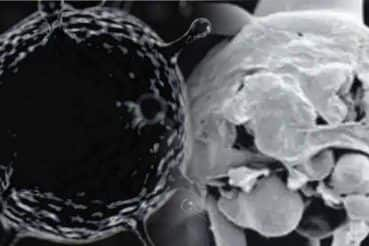

क्या है यह ब्लैक फंगस जो ले रहा है जान

स्वास्थ्य विभाग के मुताबिक ब्लैक फंगस (म्युकर माइकोसिस) एक फंगल संक्रमण है। यह उन लोगों को ज्यादा प्रभावित करता है जो दूसरी स्वास्थ्य समस्याओं से ग्रसित है और दवाईयां ले रहे हैं। इससे उनकी प्रतिरोधात्मक क्षमता प्रभावित होती है। यदि यह फंगस शरीर के अन्दर चला जाता है तो उसके साइनस या फेफड़े प्रभावित होंगे। इसकी वजह से गम्भीर बीमारी हो सकती है। यदि इस बीमारी का इलाज समय पर नहीं किया गया तो यह घातक हो सकती है।

आंख, नाक में दर्द और आंख के चारों ओर लालिमा, नाक का बंद होना, नाक से काला या लाल तरल द्रव्य निकलना, जबड़े की हड्डी में दर्द होना, चेहरे में एक तरफ सूजन होना, नाक अथवा तालु काले रंग का होना, दांत में दर्द, दांतों का ढीला होना, धुंधला दिखाई देना, शरीर में दर्द होना, त्वचा में चकत्ते आना, छाती में दर्द, बुखार आना, सांस की तकलीफ होना, खून की उल्टी, मानसिक स्थिति में परिवर्तन आना।

ऐसे कर सकते हैं बचाव

ब्लैक फंगस संक्रमण से बचने के लिए डॉक्टरों ने कुछ उपाय बताए हैं। उसके मुताबिक धूल भरे स्थानों में मास्क पहनकर, शरीर को पूरे वस्त्रों से ढंक कर, बागवानी करते समय हाथों में दस्ताने पहन कर और व्यक्तिगत साफ-सफाई रख कर इससे बचा जा सकता है।

ब्लैक फंगस के बाद अब ने मुसीबत वाइट फंगस।ब्लैक फंगस से ज्यादा घातक वाइट फंगस।

नई दिल्ली. भारत (India) में कोरोना वायरस (Coronaviurus) के बाद म्यूकरमाइकोसिस (Mucormycosis) यानि ब्लैक फंगस और अब व्हाइट फंगस ने चिंता बढ़ा दी है. बिहार की राजधानी पटना में इस नए फंगल इंफेक्शन के कुछ मामले सामने आए हैं. पंजाब, राजस्थान समेत कई राज्यों ने पहले ही ब्लैक फंगस को महामारी घोषित कर दिया है. ऐसे में व्हाइट फंगस के नए मामलों ने सरकारी और मेडिकल स्तर पर चिंताओं में इजाफा किया है. आइए इसके बारे में कुछ अहम बातों को जानते हैं-

क्या व्हाइट फंगस ब्लैक फंगस से ज्यादा घातक है?

स्वास्थ्य के जानकारों के अनुसार, ब्लैक फंगस की तुलना में व्हाइट फंगस ज्यादा घातक है. एक्सपर्ट्स बताते हैं कि ऐसा इसलिए क्योंकि यह केवल फेफड़े ही नहीं, बल्कि नाखून, त्वचा, पेट, किडनी, दिमाग, निजी अंग और मुंह को भी प्रभावित करता है.